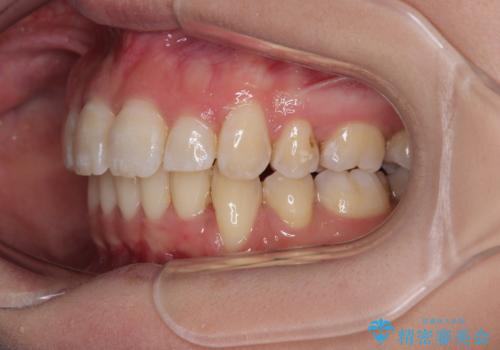

- 口元がひどく突出するくらいの上顎前突を気にして来院された患者様です。

舌の突出癖が顕著で、上顎歯列は完全なV字型となっている状態でした。

下顎歯列にも八重歯があり、上下左右の第一小臼歯4本を抜歯して、ワイヤー装置にて矯正治療を行うこととしました。

どこまで口元の突出感を改善できるのか不安でしたが、舌のトレーニングをしっかりと行ってくださり、我々も驚くほど劇的に改善することができました。